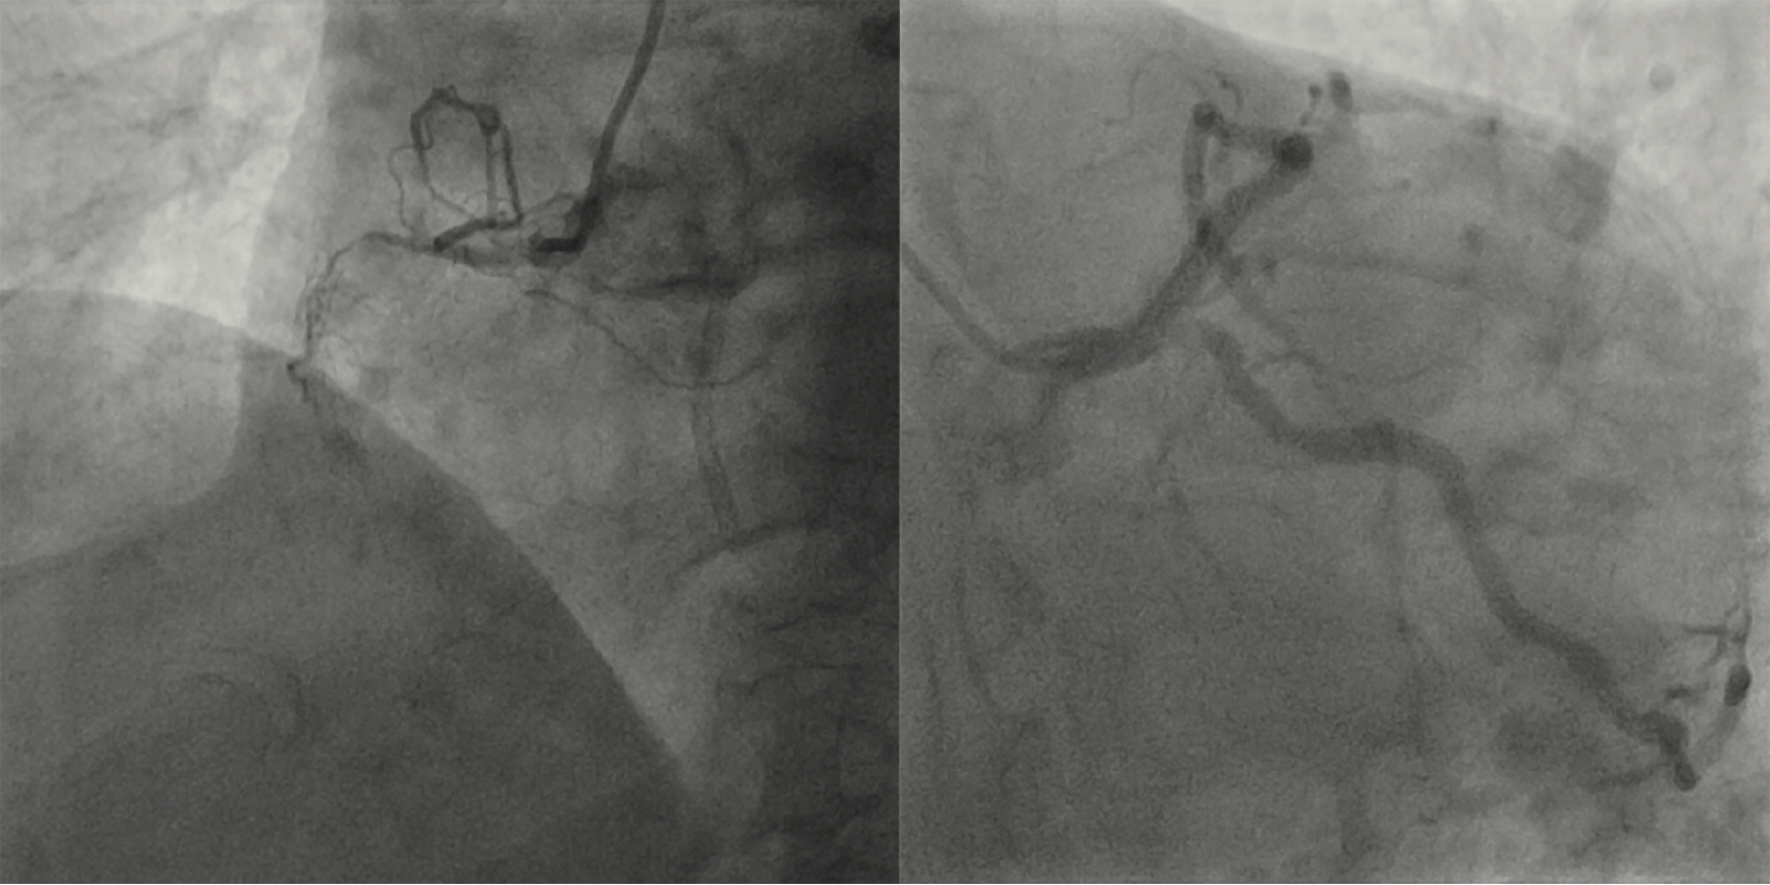

Echocardiography revealed severe aortic stenosis, with a valve area of 0.6 cm², a mean gradient of 34 mmHg, and a peak velocity of 4 m/s, consistent with severe AS. Coronary angiography demonstrated severe coronary artery disease, including left main (LM) stenosis and multivessel CAD (Figure 1). Given the complexity of his coronary pathology, he was deemed unsuitable for traditional coronary artery bypass grafting (CABG) due to the high surgical risk associated with both his coronary disease and comorbidities.

Coronary angiography revealed critical stenosis of the left main coronary artery and significant disease in the left anterior descending (LAD) and left circumflex (LCx) arteries. A double-barrel technique was successfully employed to stent the left main bifurcation, with optimal angiographic results achieved.